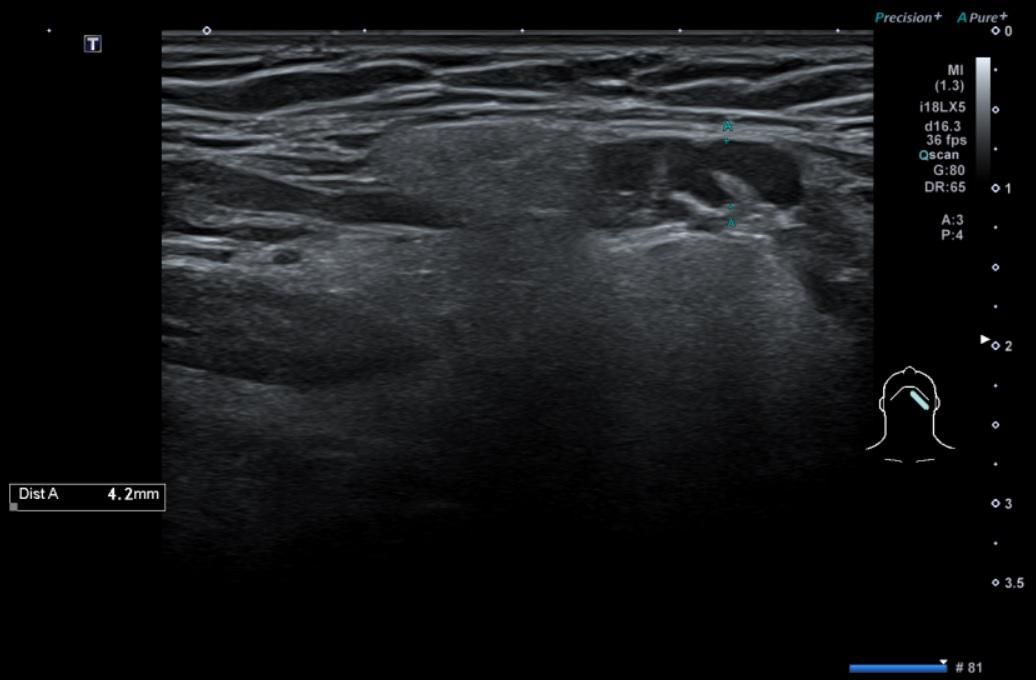

• 4번 째 사진